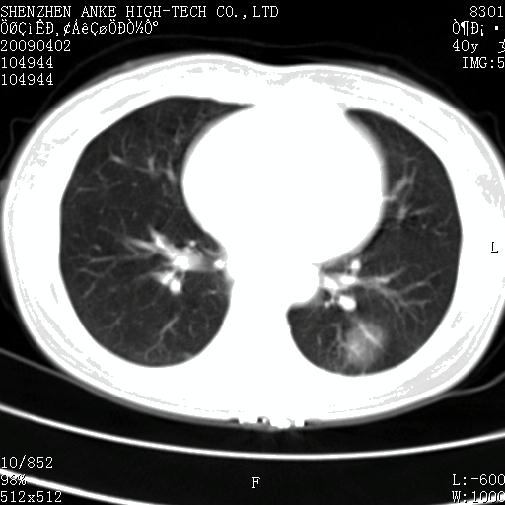

以下是引用随光逐影在2009-4-2 12:16:00的发言:[br]考虑左肺下叶背段继发性肺结核,结核球形成;建议追踪复查。

以下是引用gudu医生在2009-4-2 11:27:00的发言:[br]周围型肺癌

以下是引用卜一在2009-4-2 13:31:00的发言:[br][br] [br] 空洞壁厚不均 胸膜凹陷征。周围型肺癌可能 不排除干酪坏死型肺结核及坏死性肉芽肿。 [br] [br]支持!

以下是引用ct诊断高手在2009-4-2 13:04:00的发言:[br]空洞壁厚不均 胸膜凹陷征。周围型肺癌可能 不排除干酪坏死型肺结核及坏死性肉芽肿。